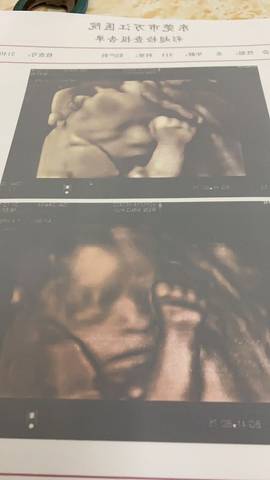

姐妹们能看出这是男孩还是女孩,其实男孩女孩都一样,就好奇,也好给宝宝准备衣服????

journal_insert_pic_1689947361journal_insert_pic_1689947367

你好,从图片上看不出宝宝的性别,不管宝宝是男孩还是女孩,只要宝宝健健康康就好,祝你心想事成

你好。我们是判断不了男宝宝跟女宝宝的,孕期定期检查,我觉得宝宝健康就好的。祝心想事成 。

亲爱的,通过这些判断不出来是什么样性别的哈,反正宝宝发育好就是最好的哈,祝你好孕。